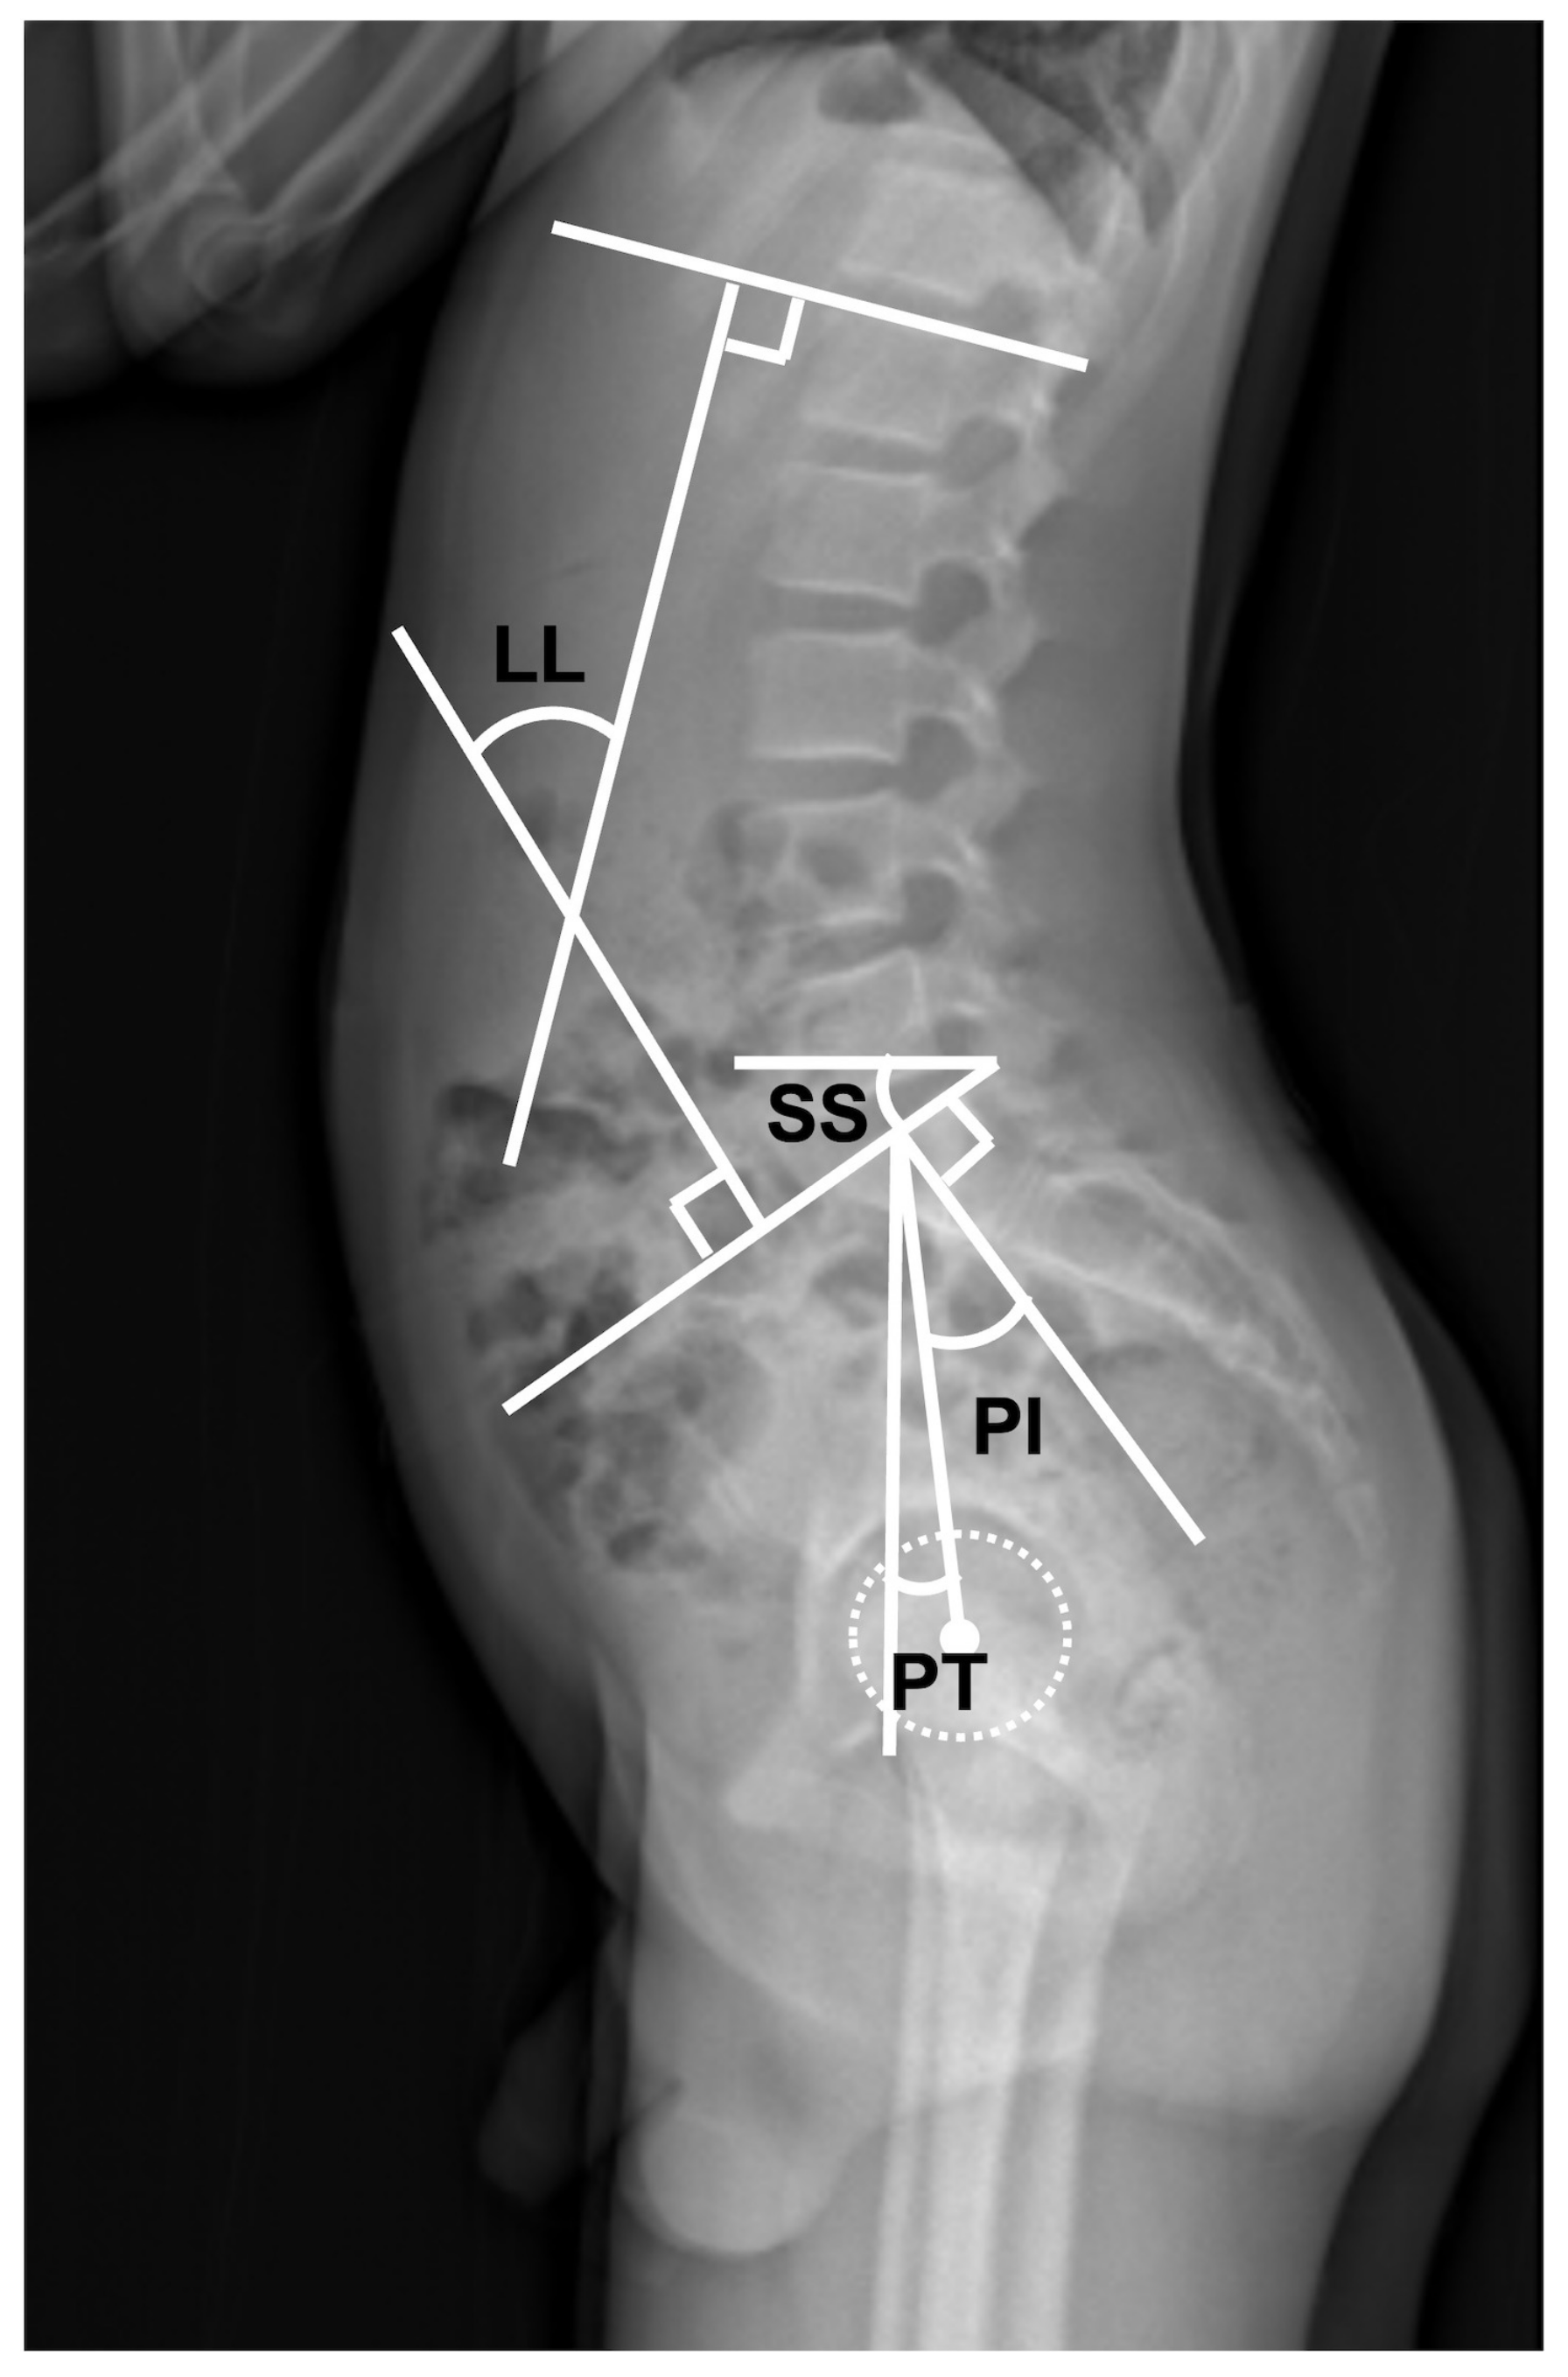

| Cobb angle (°) (SD) | 16.0 (16.4) | 5.1 (11.3) | <0.01 * |

| LL (L1–S1 level) (°) (SD) | 22.0 (18.4) | 29.7 (14.6) | 0.03 * |

| PI (°) (SD) | 51.5 (10.5) | 46.6 (9.6) | 0.03 * |

| PI–LL (°) (SD) | 29.5 (18.6) | 16.2 (15.5) | <0.01 * |

| PT (°) (SD) | 30.6 (9.3) | 21.2 (9.1) | <0.01 * |

| SS (°) (SD) | 20.9 (11.0) | 25.2 (9.4) | 0.06 |